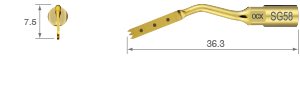

TiN coating / Dots mark 3, 6 and 9 mm from top of tip / Five teeth ; 0.6 mm thick

TiN coating / Dots mark 3, 6 and 9 mm from top of tip / Five teeth ; 0.6 mm thick /

Tips that correspond to high power can be used up to 150% power setting.

SURG 150%

TiN coating / Dots mark 3, 6, 9, 12 and 15 mm from top of tip / Five teeth ; 0.6 mm thick

The cutting part is bone torus

• POWER LEVEL [SURG] 80%

• TiN coating

• 11 teeth ; 0.6 mm thick